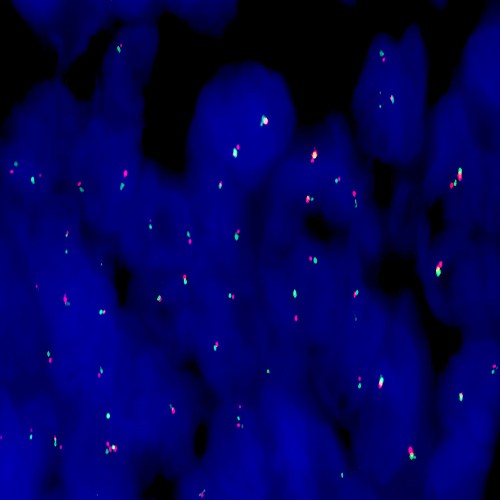

Diffuse Large B-Cell Lymphoma stained using Kreatech BCL6 (3q27) Break

XL probe for BOND (KBI-XL009).

BCL6 (3q27) Break - XL for BOND FISH probe detects genomic translocations involving the BCL6 gene. BCL6 (3q27) Proximal - XL and BCL6 (3q27) Distal - XL probes are optimized to detect the genomic regions proximal and distal to break points in the BCL6 gene region.

When combined, both probes are used to detect translocations involving the BCL6 gene at 3q27.